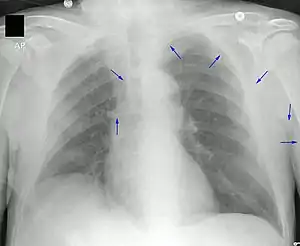

Chest X-ray showing tip of PICC line in the superior vena cava. Arrows provided to highlight the PICC line.

A PICC is inserted in a peripheral vein such as the cephalic vein, basilic vein or brachial vein in the arm, and then threaded through the veins toward the heart, until the end of the catheter rests in the proximal superior vena cava or cavoatrial junction. They must be inserted by a trained medical professional, including a physician, but also any trained medical professional such as a specially trained registered nurse.[5] An ultrasound or chest X-ray, or the use of fluoroscopy, can be used during insertion and to confirm placement. The insertion is a sterile procedure, but does not need to be performed in a completely sterile environment like an operating room.